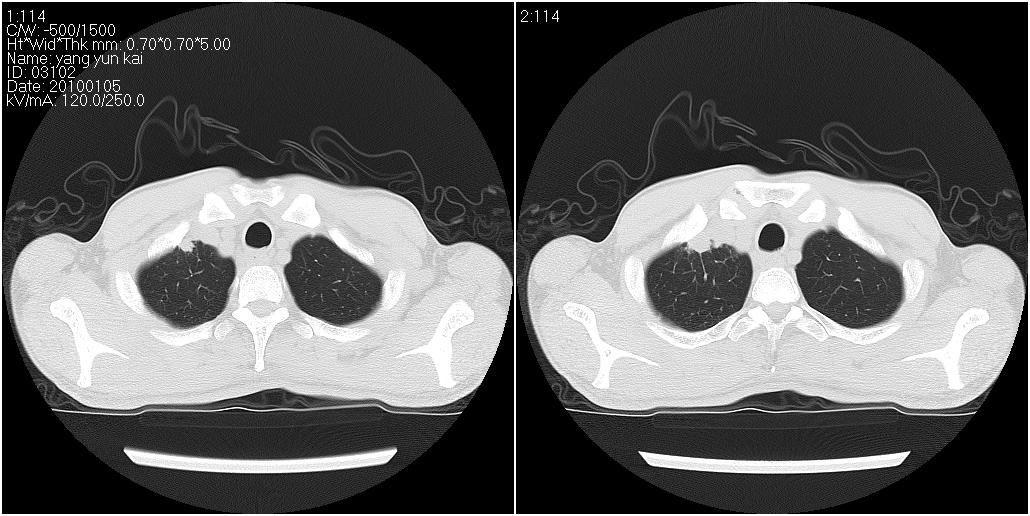

标题: CT23980:男性,47岁。近来咳痰、咳血,血沉增快(40左右),

男性,47岁。近来咳痰、咳血,血沉增快(40左右),痰中未检出结核杆菌。

两肺继发性肺结核并多发性结核球形成,部分病灶内空洞形成。

两肺继发性肺结核并多发性结核球形成,部分病灶内空洞形成

符合继发性结核表现部分空洞形成并播散